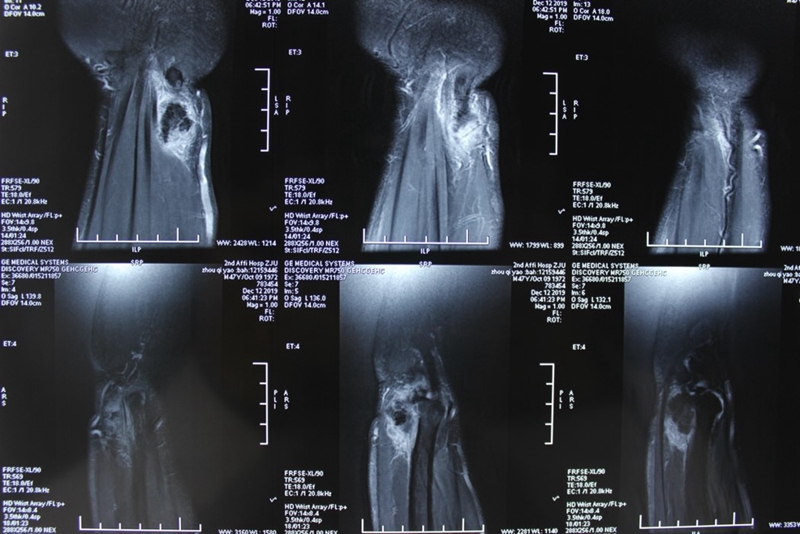

左腕关节核磁共振:左腕尺侧软组织占位